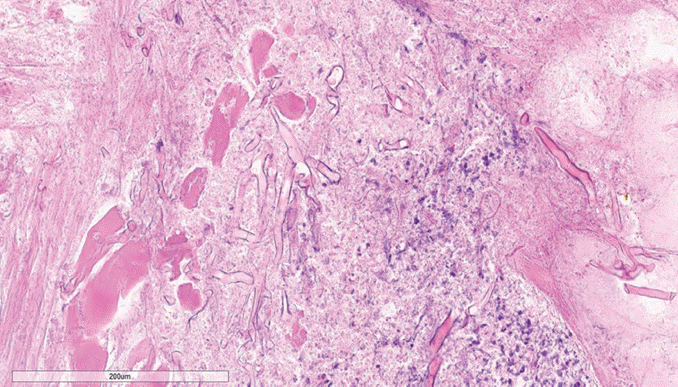

The pathologic diagnosis was confirmed as invasive mucormycosis (Fig. 2), and intravenous amphotericin B liposome (ambisome) was added to the patient’s treatment regimen. Despite management, her mental status changed to confusion with left-eye pupil dilation on the third day of admission. Brain magnetic resonance imaging showed multifocal acute ischemic lesions near the right middle cranial artery and the left corona radiata. In addition, both cavernous sinuses and internal carotid arteries appeared to be involved with invasive mucormycosis (Fig. 1E and F). Given the patient’s anticipated fatal prognosis due to disease progression and brain infarction, her family chose not to pursue further surgical interventions or diagnostic procedures. The patient developed septic shock from the progressive infection, exhibited unstable vital signs and a loss of spontaneous respiration, and passed away on the sixth day of hospitalization.

Fig. 1.

Facial photo and radiologic images of the patient. A: The initial physical examination shows blackish eschars on the right side of the face. B: Extensive debridement was performed, including the facial skin, maxillary bone, and nasal mucosa. C and D: Preoperative axial (C) and coronal (D) contrast-enhanced CT scans showed cellulitis with air formation without any definitive abscess. E: T1-weighted contrast-enhanced MRI revealed involvement of the cavernous sinus and internal carotid artery by infection. F: Diffusion-weighted imaging showed multifocal acute ischemic lesions on the right middle cerebral artery territory and the left corona radiata.